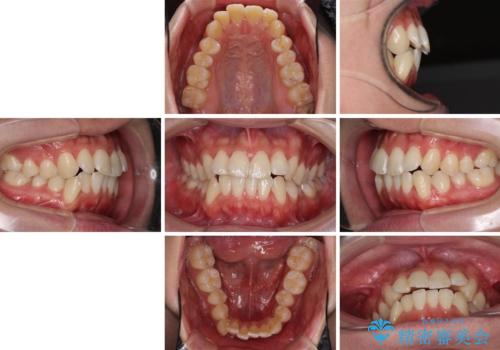

- 前歯のデコボコと若干口元が突出していることを気にして来院された患者様です。

全体的に軽微な叢生が認められ、口元もやや前方に突出していたため、インビザラインでのIPR(歯と歯の間を削る)と歯列全体の後方移動によって歯並びを整えることとしました。

上下ともに歯列の幅が狭かったため、側方に拡大することで前歯のデコボコや突出感を解消するためのスペースを獲得することができました。

歯並びが改善したことはもちろん、咬み合わせの改善まで実感することができ、患者様には大変満足していただけました。